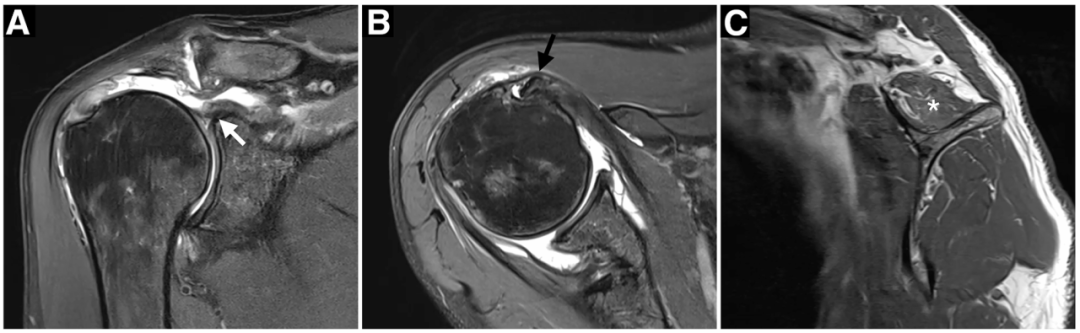

评估回缩程度和肩袖残端大小。可通过回缩的肌腱穿过一根支撑缝线来评估松解潜力。在肩峰下,以及肩袖与上盂唇之间进行肩袖松解(图 4)。

图 4. 右肩关节镜下视图,患者取沙滩椅位。(A)通过后侧入路观察间隙区,显示关节盂上缘完整的肱二头肌长头腱。(B)清创并部分切除滑囊后,观察到延伸至关节盂缘的完全性冈上肌病变。在盂唇水平切断 LHBT 后(C),尽可能松解冈上肌腱,并穿过一根缝线以利于肌腱向足迹区移动。